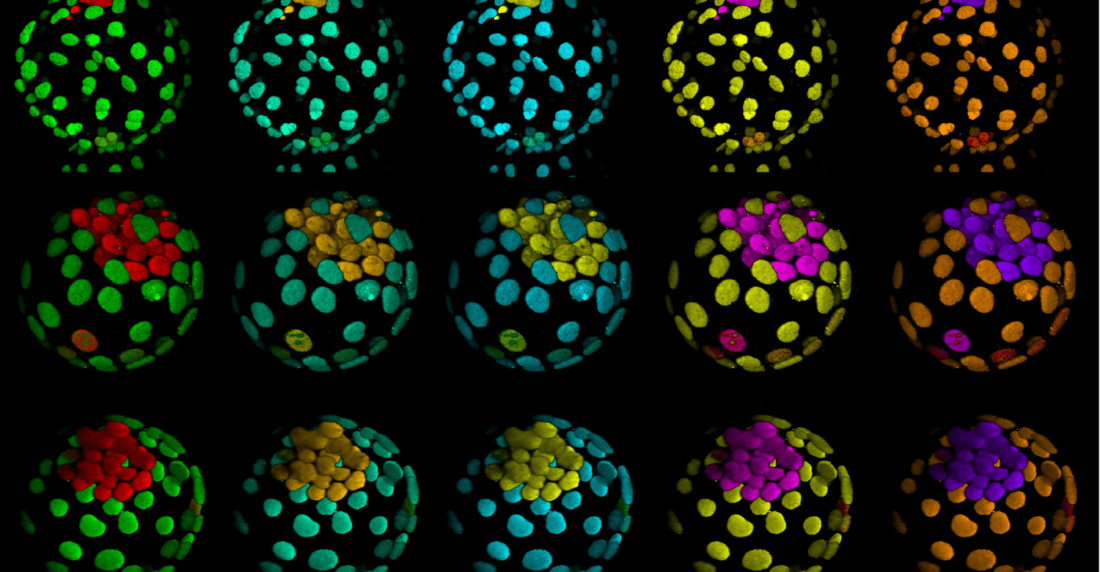

Generan embriones humanos sin óvulos ni espermatozoides

Los científicos, liderados por Magdalena Zernicka-Goetz, se basaron en células madres y desarrollaron los embriones durante 14 días. La ley británica no les permite pasar de ese tiempo

Los científicos, liderados por Magdalena Zernicka-Goetz, se basaron en células madres y desarrollaron los embriones durante 14 días. La ley británica no les permite pasar de ese tiempo

Parece una película de ciencia ficción pero es realidad: un equipo científico generó embriones humanos sintéticos sin óvulos ni espermatozoides. ¿Cómo lo hizo? Utilizando células madre.

Los científicos que lograron esta hazaña están liderados por el equipo de la Universidad de Cambridge (Reino Unido) y del Instituto Tecnológico de California (EEUU) y dirigido por Magdalena Zernicka-Goetz, la misma que publicó el pasado mes de agosto en la revista Nature cómo habían logrado reproducir fuera del útero y sin utilizar óvulos y espermatozoides lo que ocurre en las primeras etapas del desarrollo de un ratón.

«Afirman que han logrado embriones modelo, similares a los que se encuentran en las primeras fases del desarrollo humano, y que con este adelanto científico podrían encontrar respuestas a la hora de investigar los trastornos genéticos y las causas de los abortos espontáneos. Sin embargo, el trabajo viene acompañado de problemas éticos y legales», advierte Diario Médico.

En la presentación durante la conferencia de Boston, «Zernicka-Goetz describió el cultivo de embriones hasta una etapa un poco más allá del equivalente a 14 días de desarrollo para un embrión natural. En la actualidad, la ley del Reino Unido permite que los embriones humanos se estudien en el laboratorio solo hasta el día 14 de desarrollo».